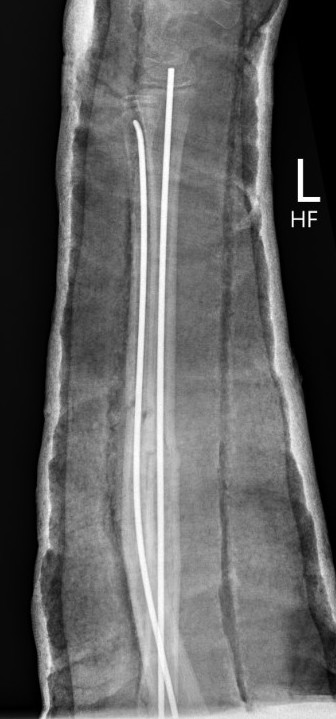

3. Intramedullary elastic nail

- smaller scars with insertion

- easier to remove than plates

Disadvantage

- generally immobilized

- must be removed

- non anatomical reduction compared with plates with theoretical risk of loss supination / pronation

- risk of extensor tendon rupture due to prominence of nails at insertion sites

TENS technique

Technique

Radius (typically first as more difficult to reduce)

Entry point with awl 2 cm proximal to distal physis

Elastic Nail size

60 - 70% of the intramedullary canal

Typically 1.5 - 2.5 mm

Fracture reduction

Avoid passing nails incorrectly multiple times as may cause compartment syndrome

Bend tip of elastic nail

May need small open reduction

Cut nail

Withdraw 1 cm, cut with endcutter, then advance

Ulna (usually reduced after radius fixation)

Entry point 2 cm distal to apophyseal plate

1. Proximal lateral

- avoids ulna nerve

3. Distal medial

Postoperative

Cast in supination to tighten interosseous membrane

Cast 6 weeks

Removal of TENS at 4 - 6 months once osseous union established